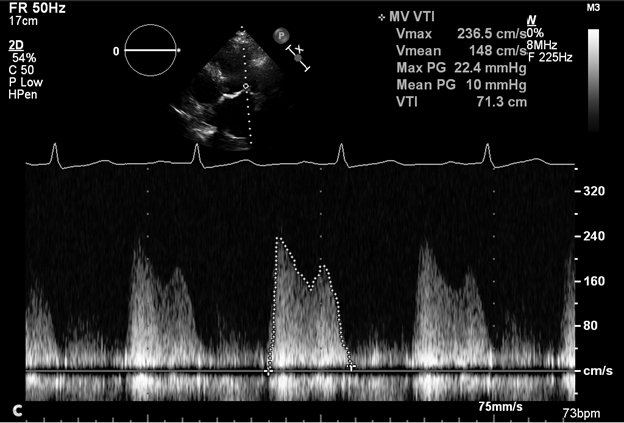

She was diagnosed with severe mitral stenosis (Image 1a) due to mitral annular calcification (MAC) (Image 1b) with a mean gradient of 10 mm Hg (Image 1c) and moderate pulmonary hypertension (pulmonary artery systolic pressure 45 mm Hg). Due to high surgical risk (Society of Thoracic Surgeons score >8%),1 transcatheter mitral valve replacement (TMVR) in MAC was planned.2 To ensure procedural success, transcatheter heart valve (THV) sizing was performed using multidetector computed tomography (MDCT) and the residual area of the left ventricular outflow tract (neoLVOT) was measured using virtual THV modeling (Image 2).

Image 1c: Transthoracic echocardiogram reveals a mean transmitral gradient of 10 mm Hg at a heart rate of 73 bpm

Image 1c